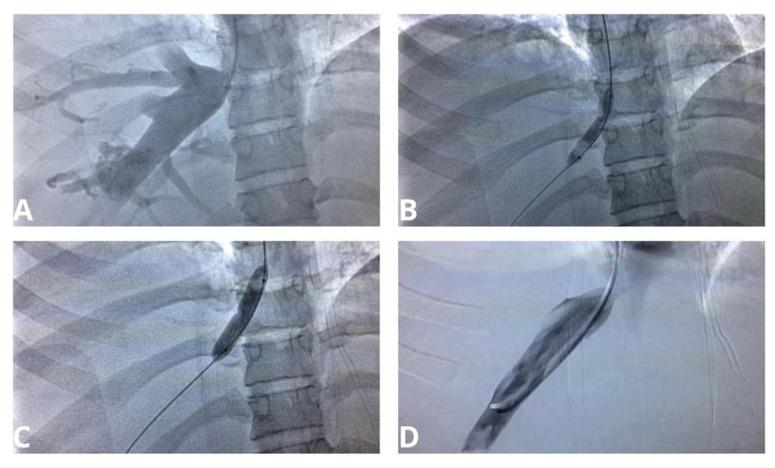

The Budd-Chiari syndrome is a rare hepatic venous disease. It is more prevalent in young adults and may present in acute, subacute, or chronic forms, causing portal hypertension. Traditional treatment consists of thrombolysis techniques and transjugular intrahepatic portosystemic shunt, as a bridge to liver transplantation. Recently, use of balloon or stent angioplasty techniques has been reported for treatment of this condition. In this article, we report and discuss a case of BCS by membranous obstruction in the hepatic vein outflow tract, with middle hepatic vein thrombosis, in a 24-year-old patient. The treatment chosen and employed was transjugular balloon angioplasty, which achieved satisfactory results and good clinical evolution.

布加综合征是一种罕见的肝静脉疾病。它在年轻成年人中更为常见,可呈现急性、亚急性或慢性形式,导致门静脉高压。传统治疗包括溶栓技术和经颈静脉肝内门体分流术,作为肝移植的桥梁。最近,有报道使用球囊或支架血管成形术技术来治疗这种疾病。在本文中,我们报告并讨论了一名24岁患者因肝静脉流出道膜性梗阻伴肝中静脉血栓形成而导致布加综合征的病例。所选择并采用的治疗方法是经颈静脉球囊血管成形术,取得了满意的效果和良好的临床进展。